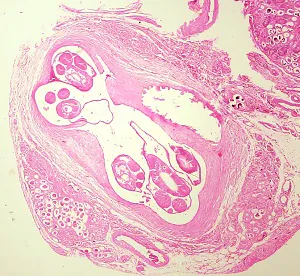

In humans, Angiostrongylus eggs and larvae remain sequestered in tissues and do not appear to be excreted in stool. A. costaricensis infections are predominantly abdominal; both eggs and larvae (occasionally adult worms) can be identified in biopsy or surgical specimens of intestinal tissue, where the eggs and larvae typically are engulfed in giant cells and/or granulomas.

The larvae of A. costaricensis in tissue sections need to be distinguished from larvae of Strongyloides . A. costaricensis first-stage (L1) larvae tend to be slightly smaller in diameter than S. stercoralis third-stage (L3) larvae and have single lateral alae, whereas S. stercoraliss L3 larvae have minute double lateral alae. The alae can be difficult to discern in most histologic sections. However, the presence of granulomas containing thin-shelled eggs and/or larvae generally serves to distinguish A. costaricensis infections from Strongyloides infections.